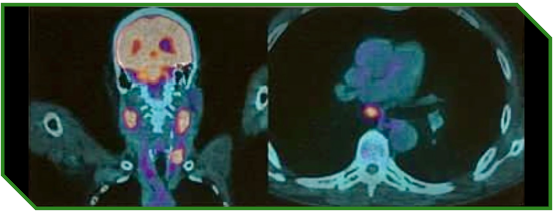

Paciente masculino de 70 anos, previamente hígido, diagnosticado com carcinoma espinocelular de laringe em estágio IVc, com acometimento metastático ósseo e pulmonar ao diagnóstico, ECOG‑PS 1 e expressão de PD‑L1 (CPS 44). O manejo incluiu radioterapia paliativa para controle de dor óssea, seguida de tratamento sistêmico de primeira linha baseado em imunoterapia associada à quimioterapia, com posterior continuidade em esquema de manutenção.